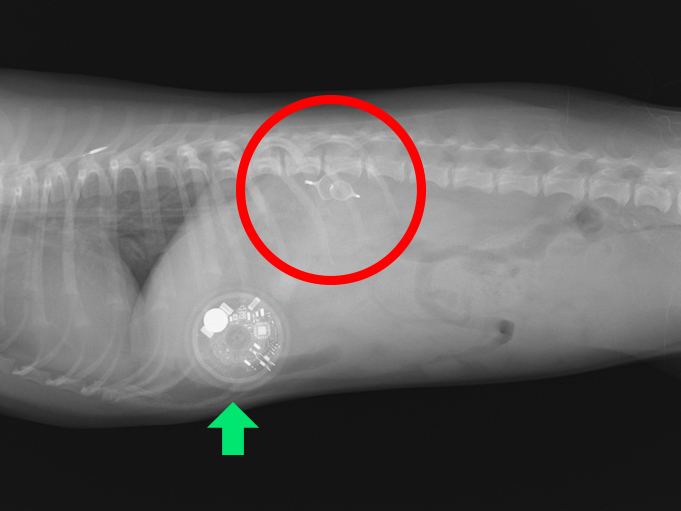

術後のレントゲン画像(赤丸がプラグ、緑矢印は血糖値の測定装置)